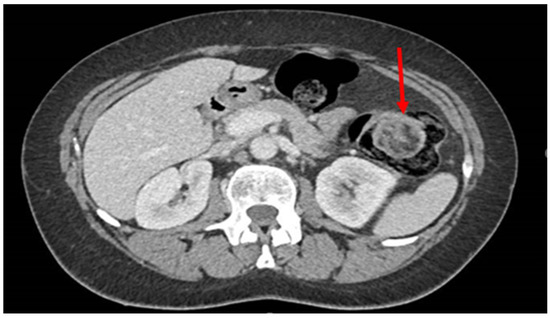

- 7 cases in which the lipoma was presumably associated with symptoms including abdominal pain, hematochezia, and even intussusception. In 3 of these cases, we had a pre-treatment diagnosis as the symptoms required the execution of pre-endoscopic radiological examinations.

| Case 4 | F | 51 | TC-colonoscopy | 6 cm | descending colon | Surgical | 1 |

| Case 6 | M | 61 | TC-RMN-colonoscopy | 5 cm | sigma | Surgical | 0 |

| Case 18 | F | 44 | TC-colonoscopy | 5.5 cm | transverse colon | Surgical | 0 |